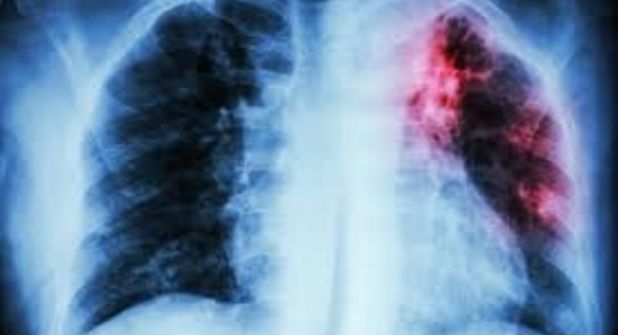

Mientras que 44 pacientes luchan por erradicar de sus cuerpos la tuberculosis, dos no lo lograron, al complicarse su salud por las enfermedades agregadas que padecen como la diabetes y el VIH y sida, ayer en el Día Mundial de la Lucha contra la Tuberculosis personal sanitario exhorta a la población con más de dos semanas de tos acudir al médico para que sean valorados y a través de la baciloscopia confirmar o descartar este padecimiento.

Comentó que debe de tenerse concientización sobre este padecimiento, sobre todo los que están al frente de esta lucha, ya que es una enfermedad milenaria que está presente desde su descubrimiento que fue en el año de 1800: “Todos los que estamos aquí en frontera somos endémicos por diversas situaciones de tipo social, migración, por pacientes de VIH, son justamente los pacientes de VIH y los diabéticos los que más preocupan por que son el grupo de pacientes más vulnerables, por lo hoy estamos en un curso internacional de esta patología, una actualización y tratamientos nuevos”.